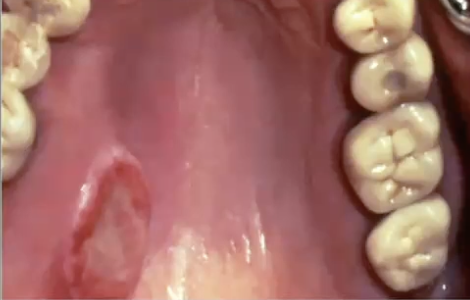

<p>What is the diagnosis?</p>

What is the diagnosis?

Nicotine stomatitis

Necrotizing sialometaplasia